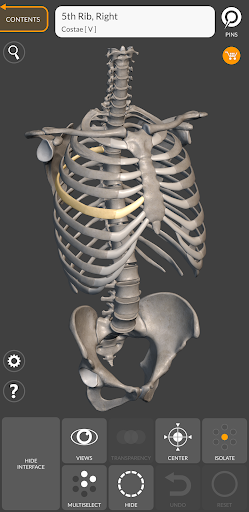

"Skeleton | 3D Atlas of Anatomy" is a next generation anatomy atlas in 3D which gives you availability of interactive highly detailed anatomical models!

Each bone of the human skeleton has been reconstructed in 3D, you can rotate and zoom in on each model and observe it in detail from any angle.

HIGHLY DETAILED ANATOMICAL 3D MODELS

• Skeletal System

• Accurate 3D modeling

• Surfaces of the skeleton with high resolution textures up to 4K

• Rotate and Zoom every model in the 3D space

• Division by regions for a clear and immediate visual of each structure

• Possibility to hide every single bone

• Interactive Pin allow visualization of the term relative to every anatomical detail